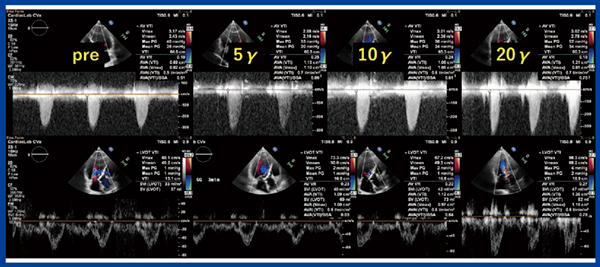

DOB負荷心エコーでは,Vmax3.6m/s,stroke volume44%,駆出率(EF)35%→52%となり,ASは中等度(偽性)と診断された(図2)。2回目のTAVIカンファレンスでは,左室収縮予備能低下の原因が問題となったが,CAGで虚血は否定されており,少なからずASが影響していると考えられた。今後,COPDの増悪に対する治療が必要になる可能性も考慮し,ASの解除を目的にTAVIを施行した。

図2 症例1のDOB負荷心エコー